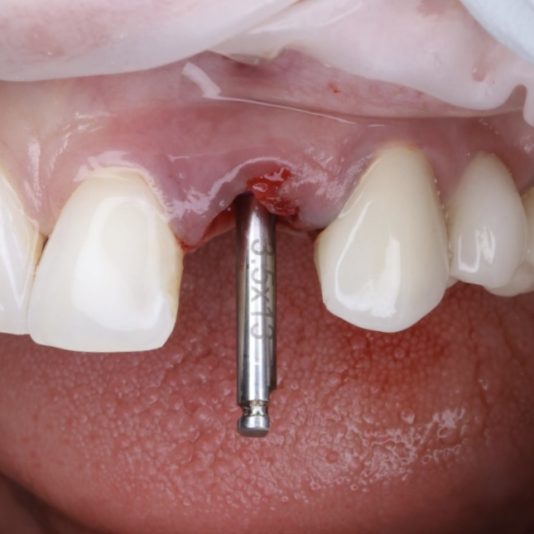

Tip I am grateful to have been taught early by my mentor: Check Your Pilot Drill Angulation Early.

When placing implants, taking a PA X-ray of the pilot drill is a crucial step that’s often overlooked. This simple check can save you from a lot of headaches down the line.

If you notice angulation issues, the good news is that they’re easily corrected at this stage. You can use a lance drill to adjust the path before moving to wider drills. Once you progress past the pilot stage, corrections become much harder and risk compromising the implant site.

Early course corrections have saved me time, reduced my stress, and lead to better outcomes for me and my patients. Don’t skip this critical step! Of course if you take a CBCT it’s even better, but maybe not as practical. Happy Thanksgiving Everyone!